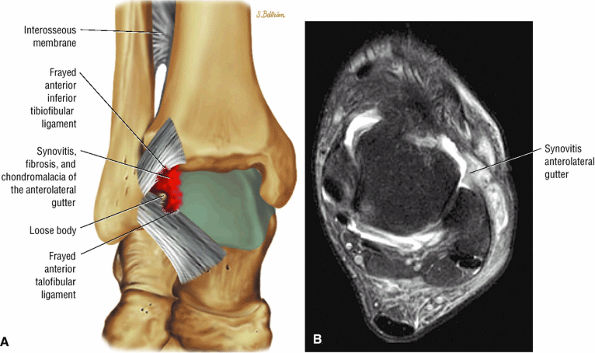

FIGURE 5.29 Impingement.